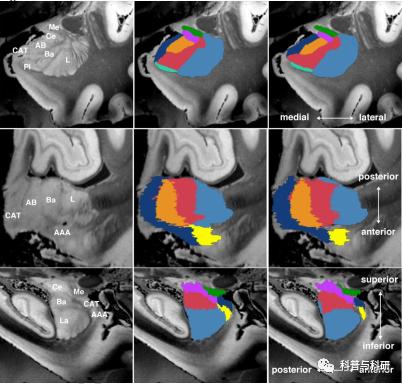

皮下核团体积提取 |

1、海马亚区分割、杏仁核分割 2、皮下核团体积提取 3、特定脑模板皮层厚度提值 4、格式转换 |

(3)皮下核团体积提取

如海马亚区体积计算提取、杏仁核体积计算提取等